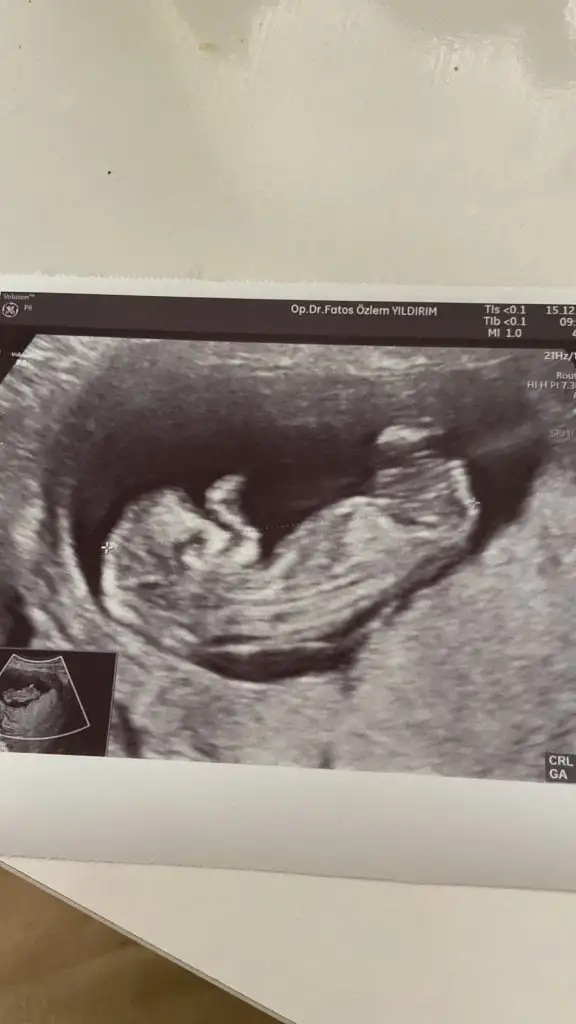

Bende 11+2 deyim doktorum tahminde bulundu ve erkek dedi ama ben hiç erkek hissetmiyorum bu zamana kadar sivilce çıkmayan yüzümde alnımda 4 tane sivilce çıktı ultrason fotoğrafını bırakıyorum Kızlar bana da bir tahmin de bulunsanız